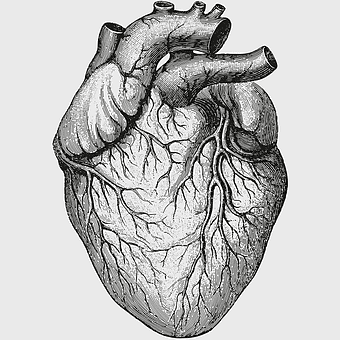

human heart diagram, monochrome anatomy drawing, black and white heart illustration, human organ sketch, cardiovascular system diagram, medical illustration heart, heart structure outline -

Heart Anatomy Diagram, human heart drawing, realistic heart illustration, cardiovascular system, medical illustration, organ structure, human anatomy study -

human heart illustration, cardiac anatomy diagram, heart blood vessels, medical organ visuals, cardiovascular system chart, human anatomy study, circulatory system illustration -

heart sketch, human heart anatomy, monochrome organ drawing, patricia visser art, cardiovascular system illustration, medical biology diagram, black and white anatomy chart -